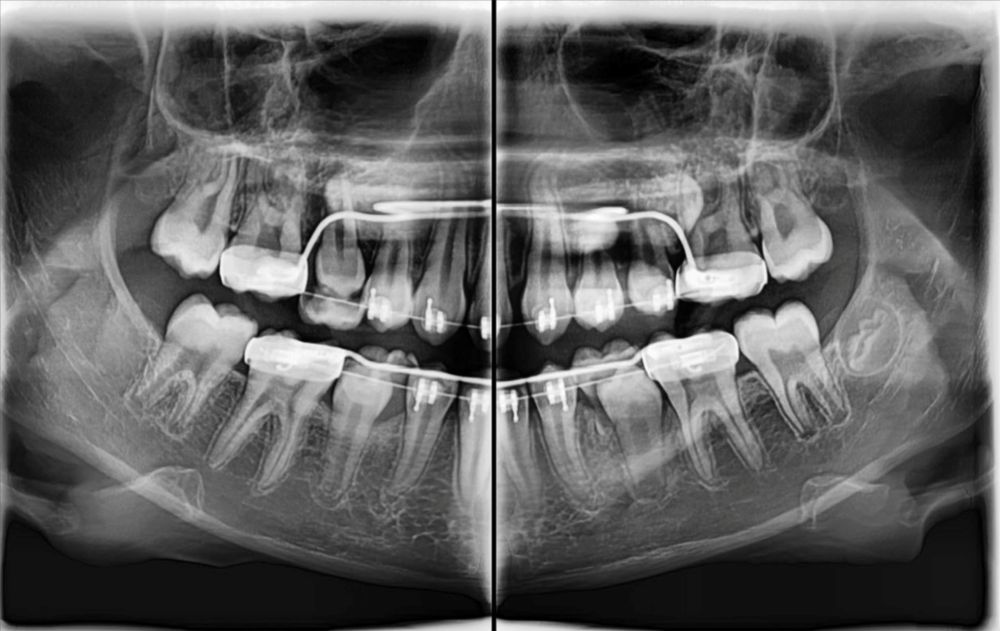

- wyraźne obrazy 2D i 3D — pomocne przy implantach, ósemkach, leczeniu kanałowym i ortodoncji

Pantomogram pokazuje cały stan uzębienia i kości — dzięki temu można wykryć zmiany, których nie widać na małym zdjęciu punktowym (jak torbiele, stany zapalne czy problemy ze stawami). To proste badanie, które warto wykonać profilaktycznie co kilka lat.